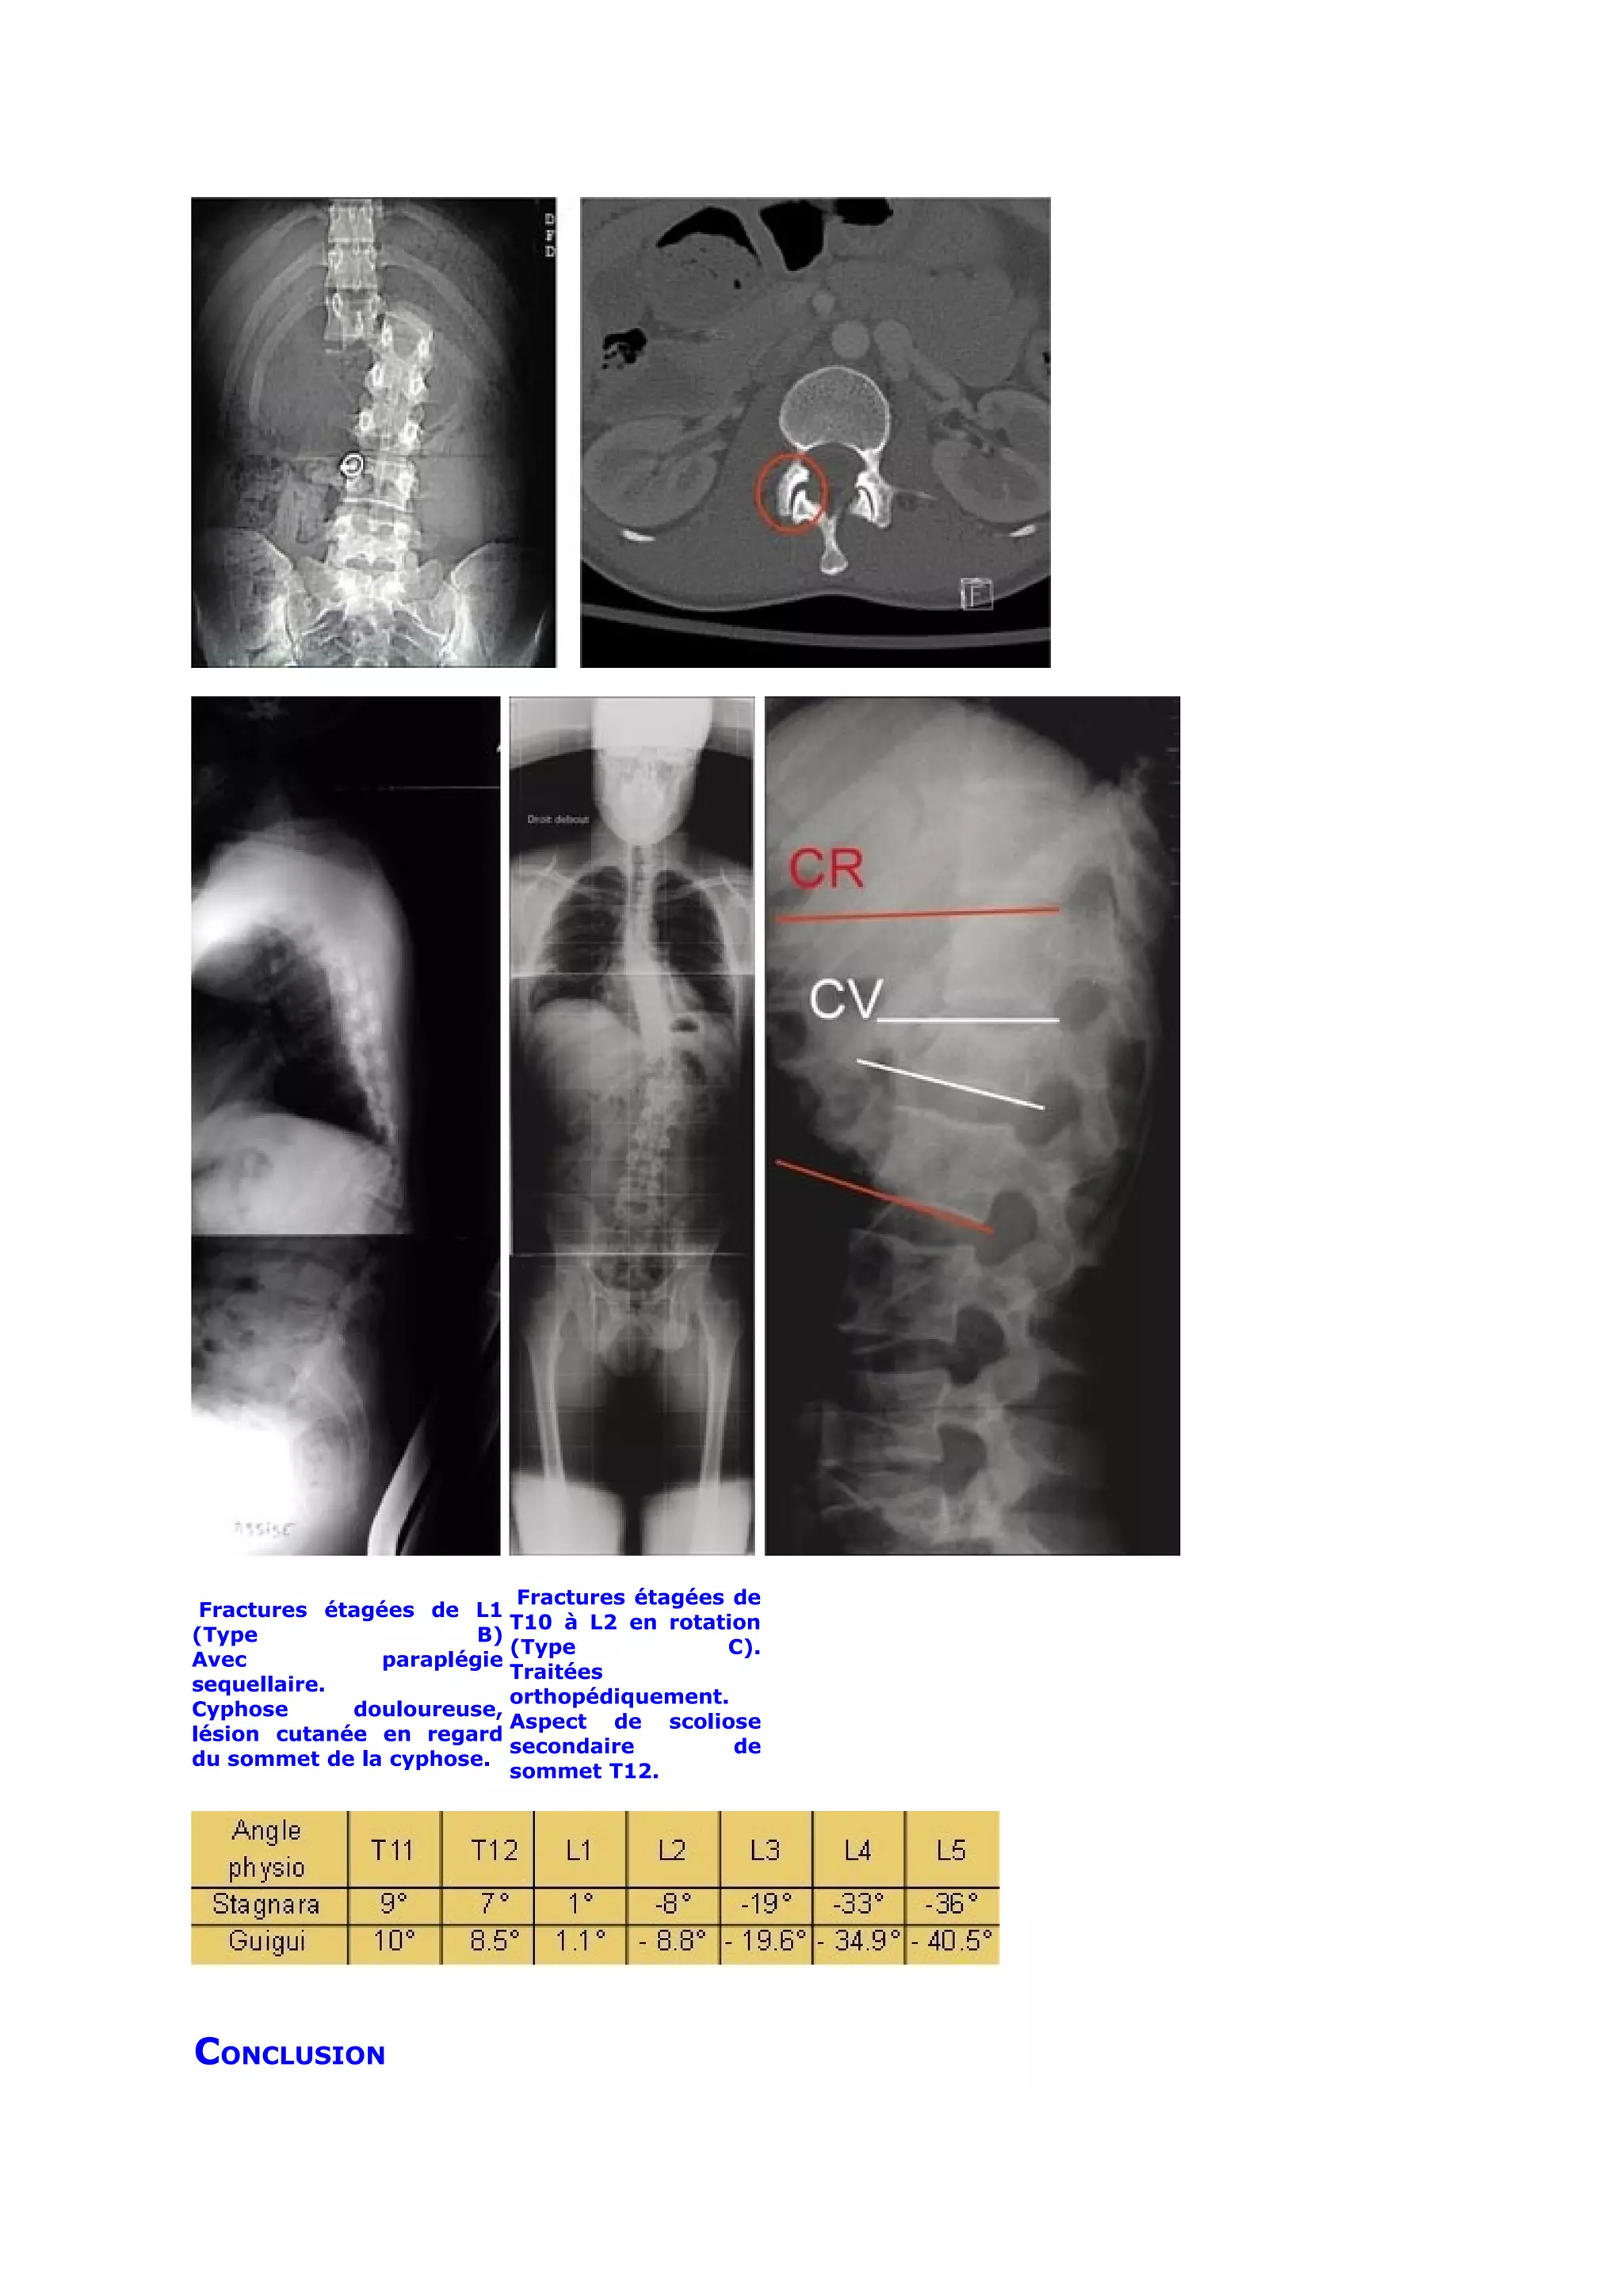

Fractures étagées de

Fractures étagées de L1

T10 à L2 en rotation

(Type                  B)

(Type             C).

Avec           paraplégie

Traitées

sequellaire.

orthopédiquement.

Cyphose      douloureuse,

Aspect de scoliose

lésion cutanée en regard

secondaire         de

du sommet de la cyphose.

sommet T12.